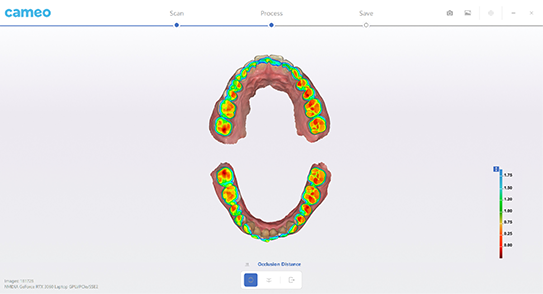

Bite check

|